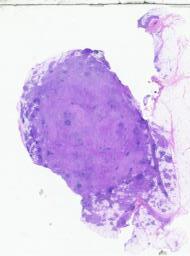

临床资料: 男,54岁,发现颈部两处肿物1年。双侧颈部局部探查:局部皮下软组织结构层次清晰,右侧颈部内可见一大小约24×8mm的淋巴结样回声,边界清,内回声不均匀血流信号,上述部位未见明显异常血流信号距体表约5mm。左侧颈部内可见数个淋巴结样回声,边界清,内回声不均匀,其中一个大小约6×5mm。CDFI:上述光团内及周边未见明感检查结果:双侧颈部软组织层异常占位(考虑淋巴结增大)。

大体所见: 灰白组织2枚,直径1.8-2.5cm,切面灰白。

免疫组化: 免疫组化:Ki-67(+),CD1O(+),CD20(+),Pax-5(+),CD3(+),CD5(+)。CD23(FDC网),Bcl-2(+),Bcl-6(+),MUM1(+),CD21(FDC网),CyclinD1(-),CD43(+),S-100(+),CD68(+).